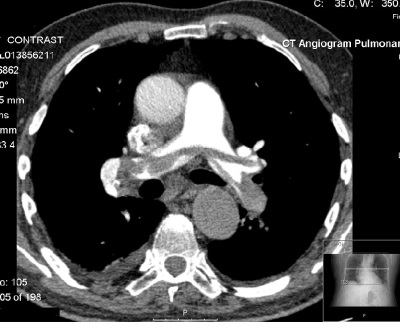

CTPA

- peripheral emboli affecting subsegmental arteries may be missed